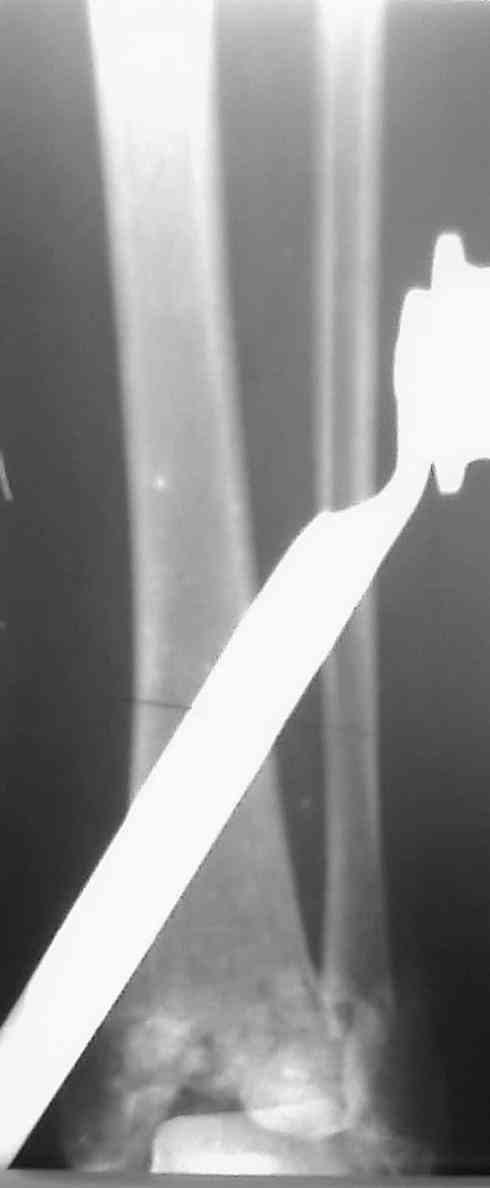

[Ortho] Перелом пилона

Уважаемые коллеги,прошу совета.

Девушка, 29 лет, падение с высоты 10 дней назад. Рентгенограммы в

приложении, КТ пока не готово, выложу по возможности.

Предполагается ORIF м/берцовой кости 1/3 трубчатой пластиной,

дистального конца б/берцовой - винтами + пластиной LCP.

Мнения коллег разошлись по следующим вопросам:1. Какие доступы выбрать,

с какого отдела начинать.

2. Облегчит ли работу дистрактор.

3. Потребуется ли костная пластика.